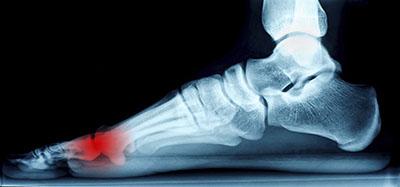

Morton's Neuroma

The pain caused by Morton’s neuroma is typically experienced at the ball of the foot. Many have described the sensation as feeling like they have a pebble stuck in their shoe. Because of this, those with the condition may find walking to be more difficult and uncomfortable. They may also experience a numbing or burning sensation in the foot. One of the most common factors that influence the development of Morton’s neuroma is improper footwear. Those who generally wear tightly fitted shoes or shoes with higher heels are more at risk at getting Morton’s neuroma. Having a foot abnormality may also increase the risk of getting this condition, as it may cause instability, thus adding more pressure onto the nerves of the foot. Certain foot conditions such as bunions, hammertoes, and flat flat feet have also been known to lead to Morton’s neuroma if not treated promptly.

Athletes have a tendency of getting Morton’s neuroma due to repetitive motions and pressure placed on the ball of the foot while running or jumping. Morton’s neuroma may also develop as a result of an injury to the foot.